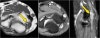

* Ulnar neuritis

There is enlargement of the nerve. On the T2W-image there is high signal.

Another sign is non-uniform enlargement of the fascicles, which is seen on the sagittal image (arrow).